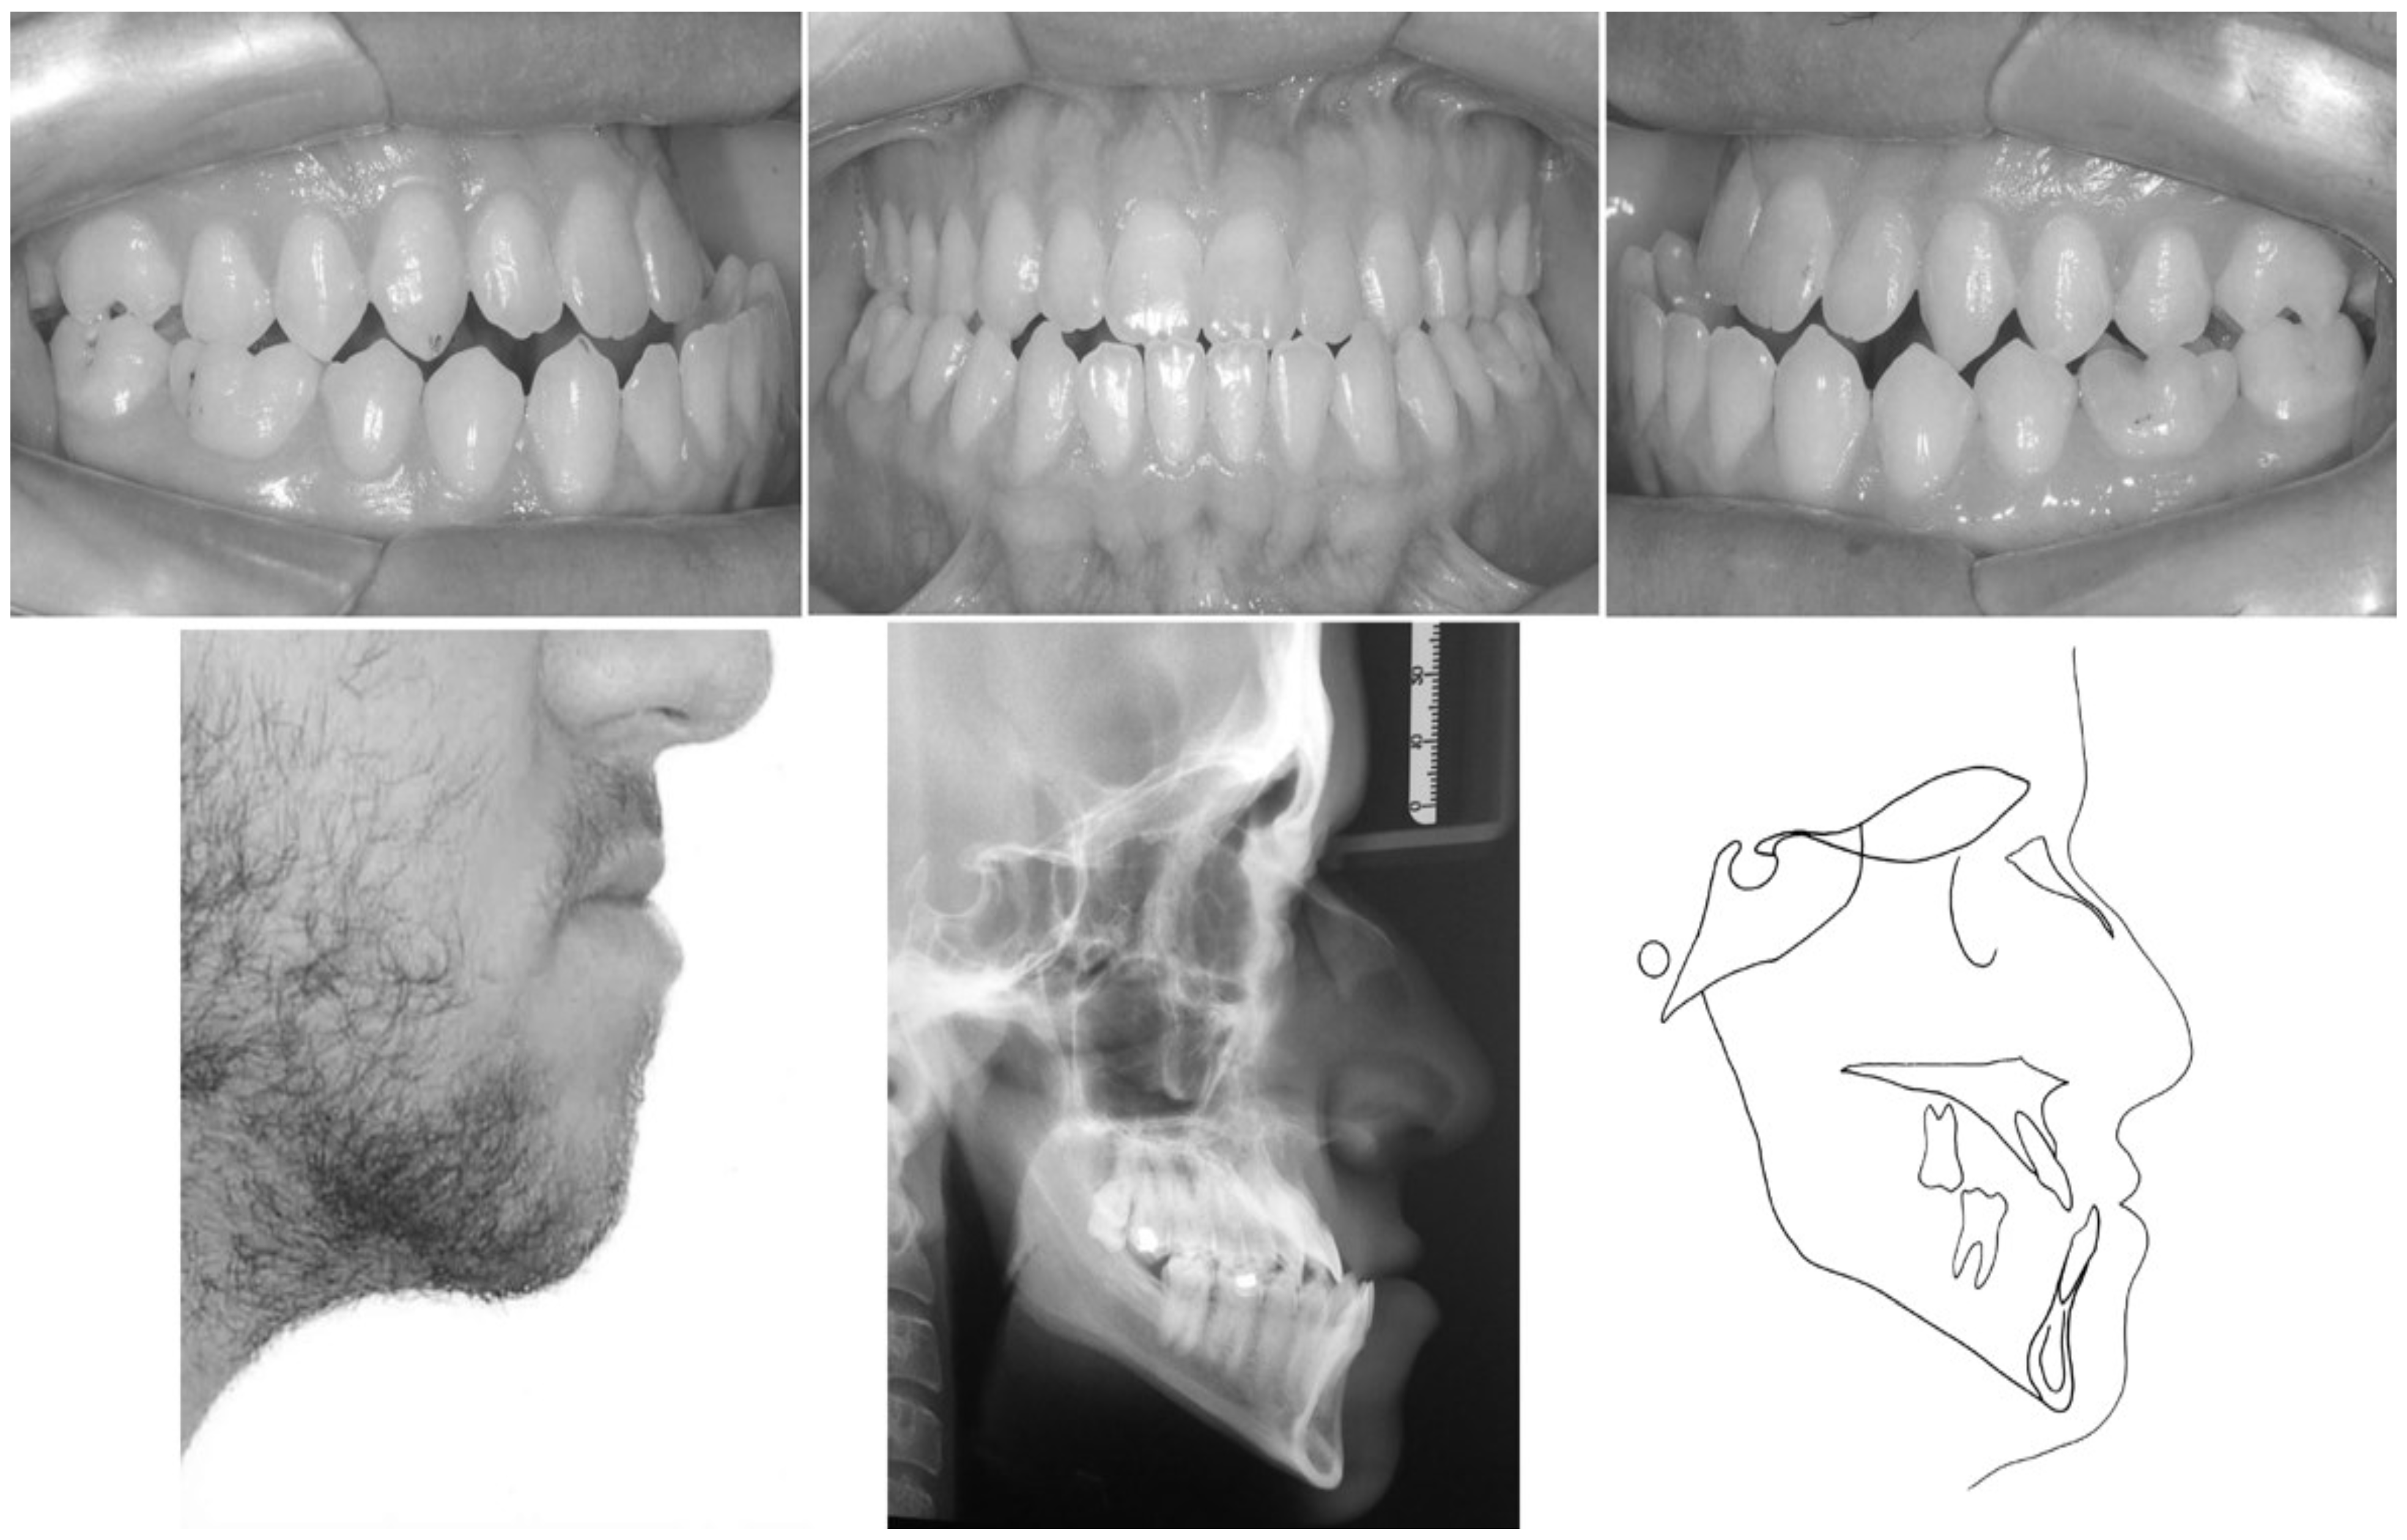

CASE REPORT